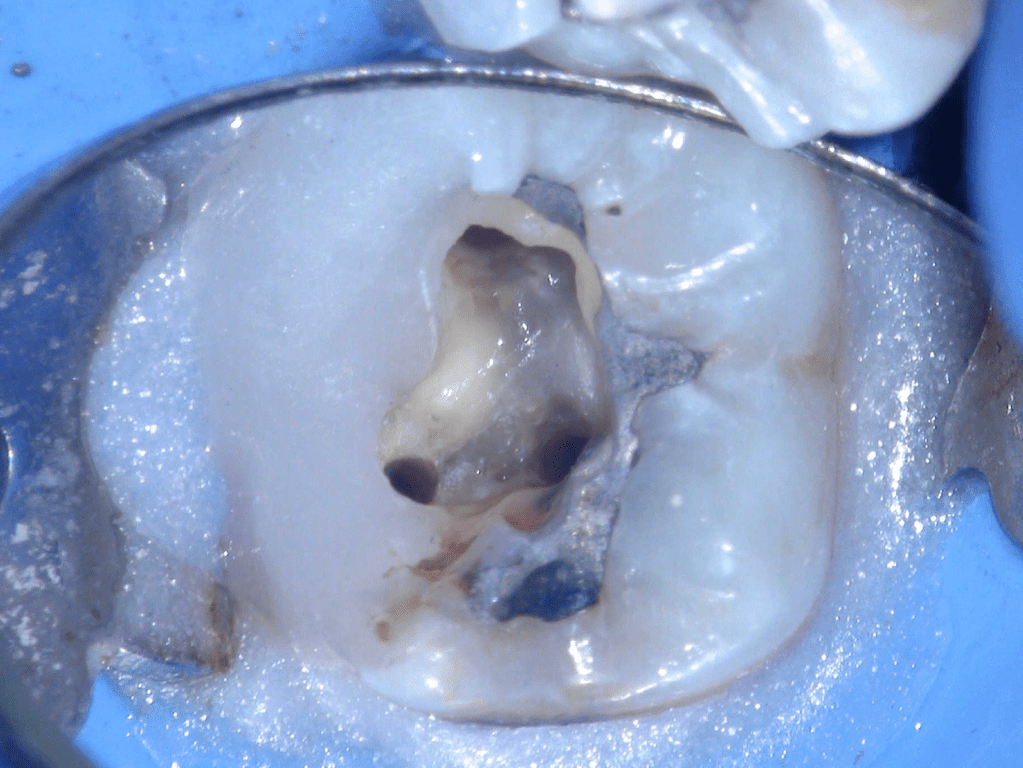

Fisura, remoción amalgama para explorar